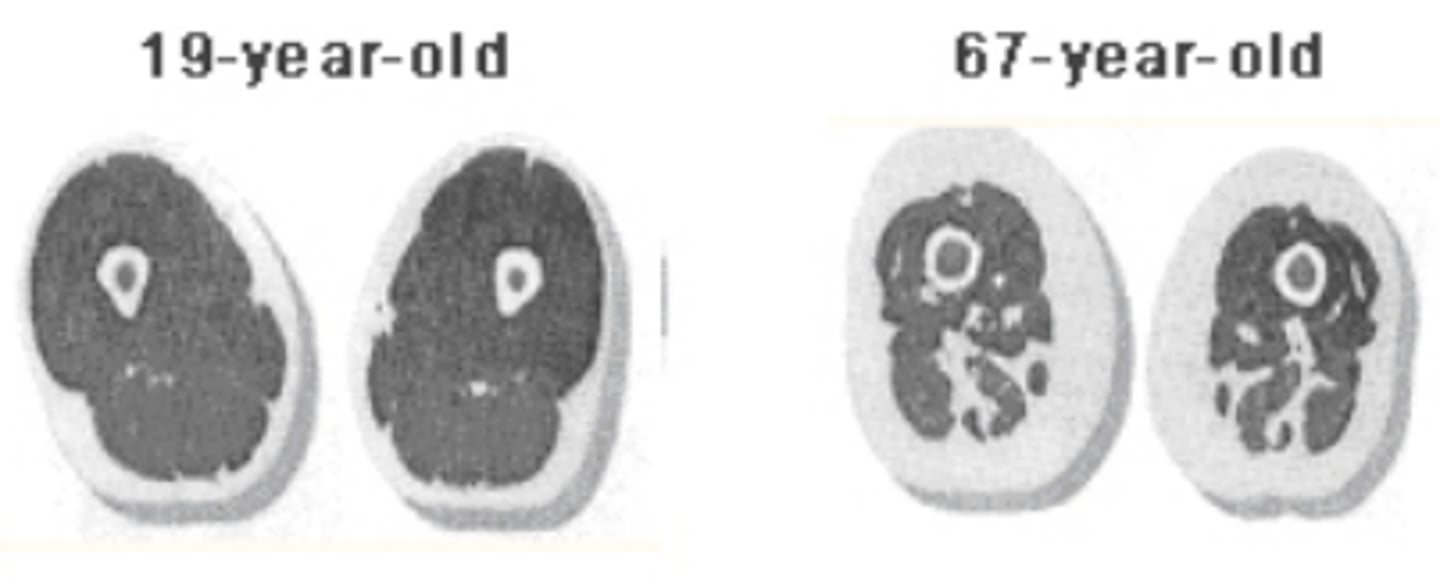

Describe what sarcopenia is

-irreversible muscle atrophy with age (starts around 30-40); why athletic performance decreases

-muscle fibers die and get replaced w/ non-contractile connective tissue (less crossbrdige formations)

-sarcopenia delayed w/ exercise